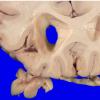

Infarct, Tract Degeneration, illustrative case (2)